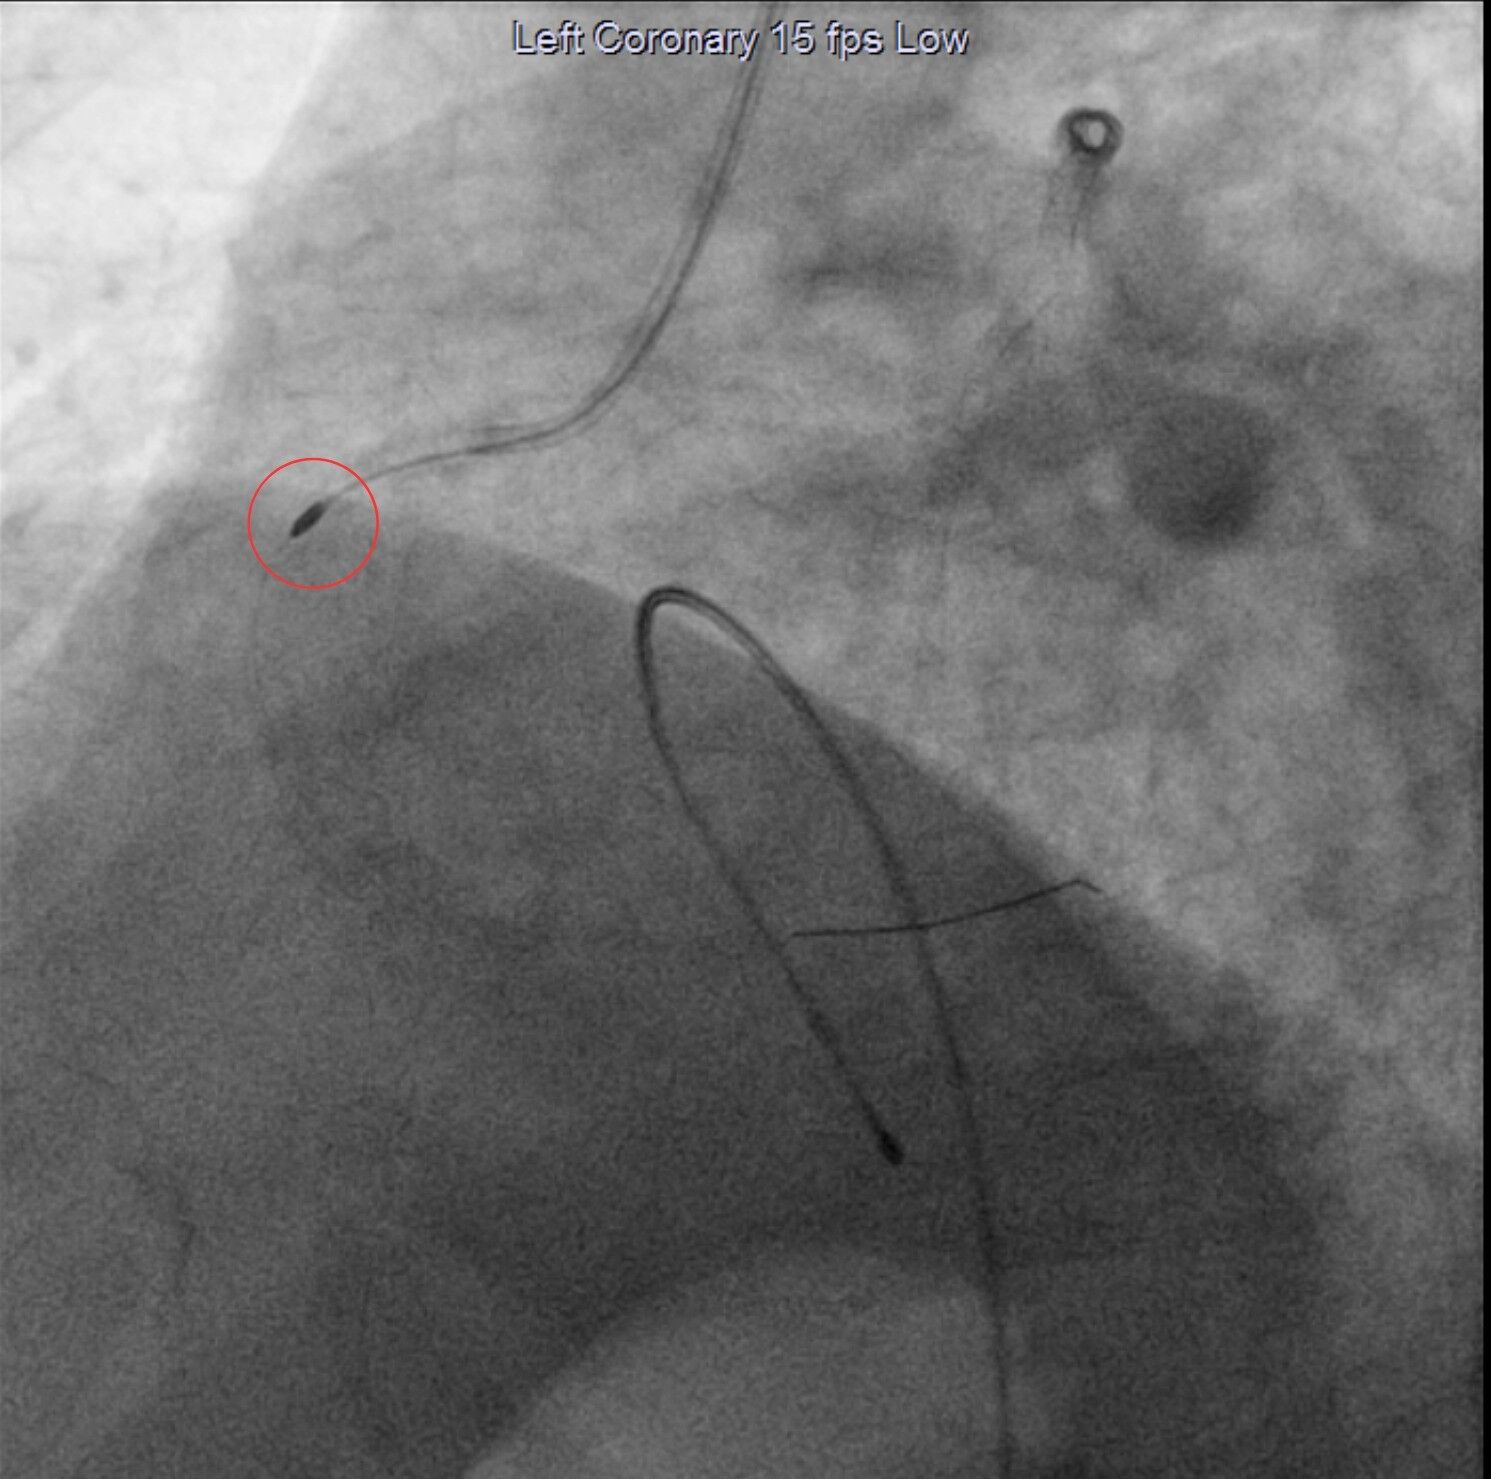

Elazığ’da hizmetlerine her gün bir yenisini ekleyen Fethi Sekin Şehir Hastanesinde, yoğun damar kireçlenmesinden dolayı stent ve balon işlemi uygulanmasında zorluk yaşanan hastalara ‘Rotablasyon Tedavisi’ yapılmaya başlandı. Dünyada yeni olan bu uygulama sayesinde önce damardaki yoğun kireç ucu elmas tozuyla kaplı bir damar içi araç ile traşlanarak temizleniyor, ardından balon ve stent takılıyor. Bu işlemle takılan stentin tedavi başarısı oldukça artıyor.

Tedavi hakkında bilgi veren Kardiyoloji Uzmanı Dr. İsmail Polat, “Bugün ikisi dış merkezden ikisi de direkt merkezimize başvuran dört hastamıza rotablatör cihazıyla rotablasyon işlemi yapacağız. Biz tıkalı damarları önce balon yapıyoruz, ardından stent takıyoruz. Bazı hastalarımıza maalesef bunları yapamıyoruz çünkü damarları çok kireçli ve çok sert oluyor. Bu hastalarda balon ve stenti geçirmek ve stenti optimal şartlarda açmak pek mümkün olmuyor. Bunlarda da şu an yeni bir teknoloji olan rotablasyon işlemi yapıyoruz. Rotablasyon işlemini rotablatör cihazı da yapıyoruz. Cihazın ucunda elmas tozu kaplı bir uç var. Kendi ekseninde dakikada 150 ile 200 bin devirle dönen cihazı tıpkı bir matkap gibi o kireçlenmiş, taşlaşmış olan o tıkalı damar bölgesine kasıktan iletiyoruz ve burayı traşlayarak bu kireçli alanı temizliyoruz. Ondan sonra balon ve stent işlemi yapıp hastayı bir gün koroner yoğun bakımda takip ettikten sonra ertesi gün taburcu ediyoruz” dedi.

Polat, “İşlem, anjiyografi laboratuvarında yapılmaktadır. Kasık veya kol damarınızdan işlem yapılabilir. Bu damarlara yerleştirilen kılıflar içerisinden kalp damarlarınıza plastik borular (kateter) yerleştirilir. Bu plastik borular yardımı ile ilgili darlığa rotablatör cihazı ilerletilir. Tıraşlama işlemi sırasında ve sonrasında normal anjiyografi uygulanarak darlığın durumu ve değişiklikler ayrıca incelenir” diye konuştu.